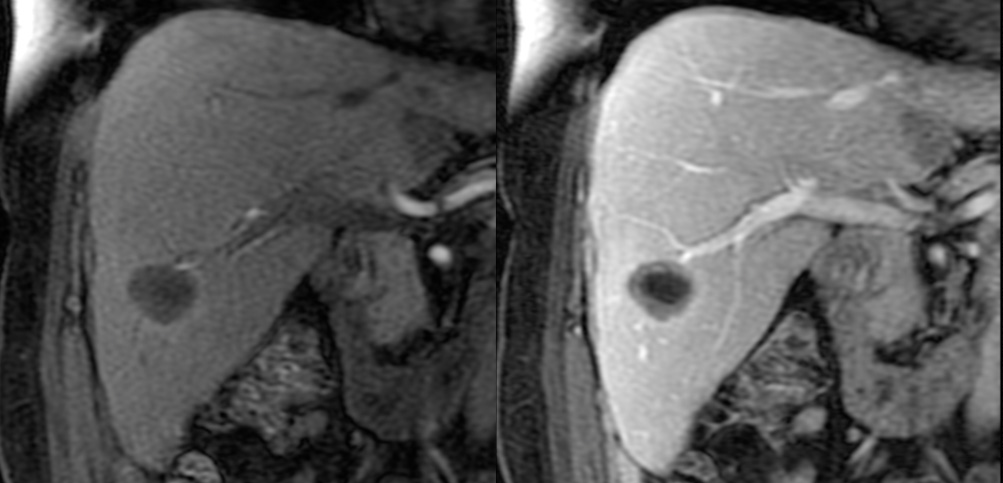

- МРТ печени. Позволяет обнаружить опухоль на самой ранней стадии развития.